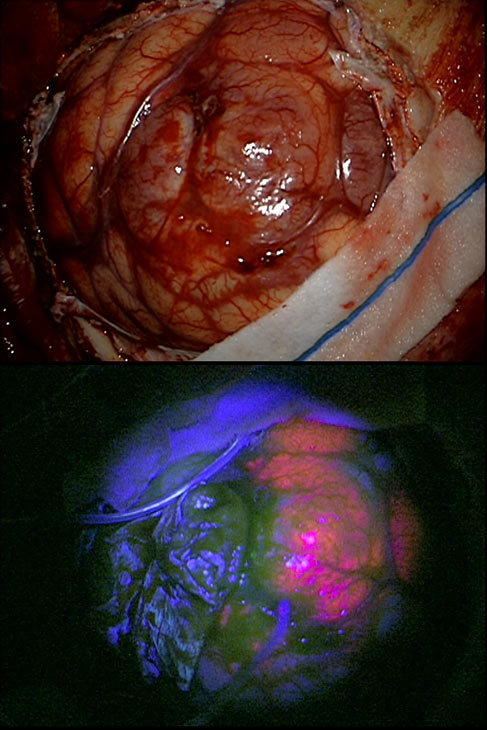

טכנולוגיות אלו מאפשרות למנתח לזהות במדויק את גבולות הגידול ולהימנע מפגיעה ברקמה בריאה. במקרים מסוימים נעשה שימוש גם בחומרים פלואורסצנטיים כגון 5ALA (ראה תמונה מס' 1). אלו מסייעים להדגיש את הגידול במהלך הניתוח ולשפר את יכולת ההסרה שלו.

תמונה מס' 1: גידול מסוג גליובלסטומה אשר עובר פלואורסנציה (תמונה תחתונה), תחת אור אולטרא סגול, לאחר מתן 5ALA .